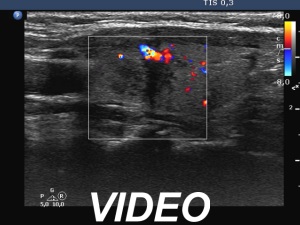

Second examination a year later (second row of images):

Ultrasonography. The thyroid has significantly decreased in size. The echogenicity became normal. The left lobe has already had discrete hypoechoic lesions but the size of them was much smaller compared with the previous visit.

3. if we had any doubts about the diagnosis after the first examination, it disappeared after the second visit: the size of the lobes decreased, the echogenicity became normal and although the discrete lesion has been already present, it also decreased in size.